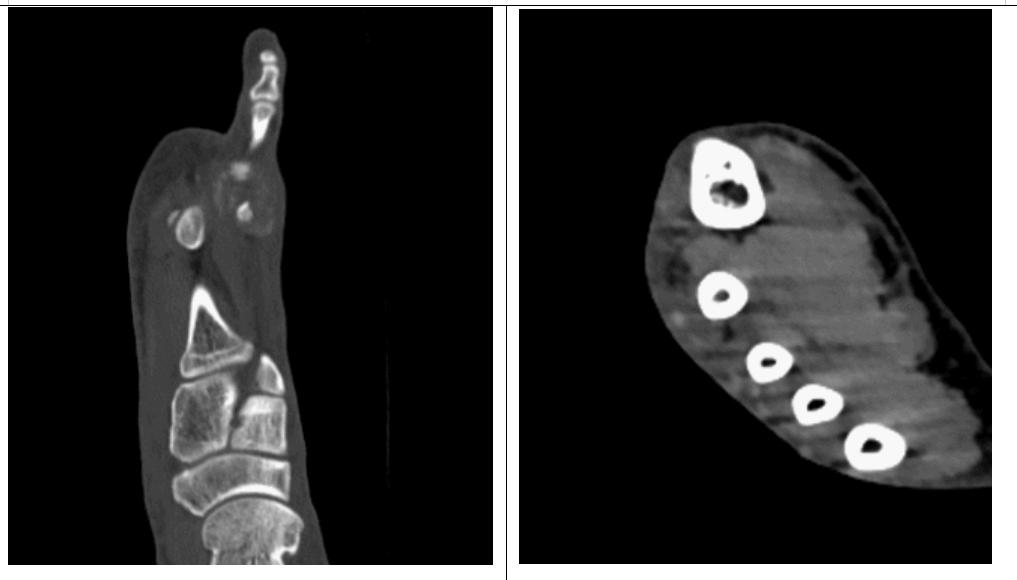

何先生的痛风石表面开起来不大,大约2cm×2cm×1cm,但是做了足部CT检查后发现其内却是“内藏玄机”。痛风石不仅存于足背皮肤表面,还存在第2、3跖骨头之间,同时还发现第2跖骨头已经出现了多处骨质囊状破坏,骨质表面已经被痛风石所“啃食”,令人不寒而栗。

图④患者足部CT检查的横截面观(左图)及矢状面观(右图)